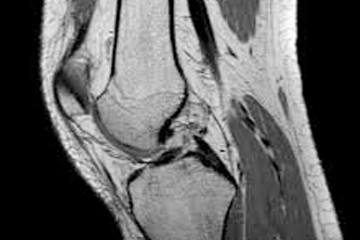

Knee MRI is increasingly used to inform clinical management. Features associated with osteoarthritis are often present in asymptomatic uninjured knees; however, the estimated prevalence varies substantially between studies. We performed a systematic review with meta-analysis to provide summary estimates of the prevalence of MRI features of osteoarthritis in asymptomatic uninjured knees.